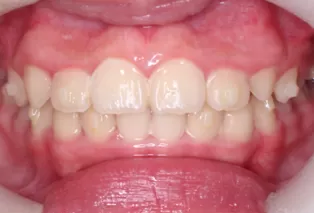

Photos intra-orales après traitement